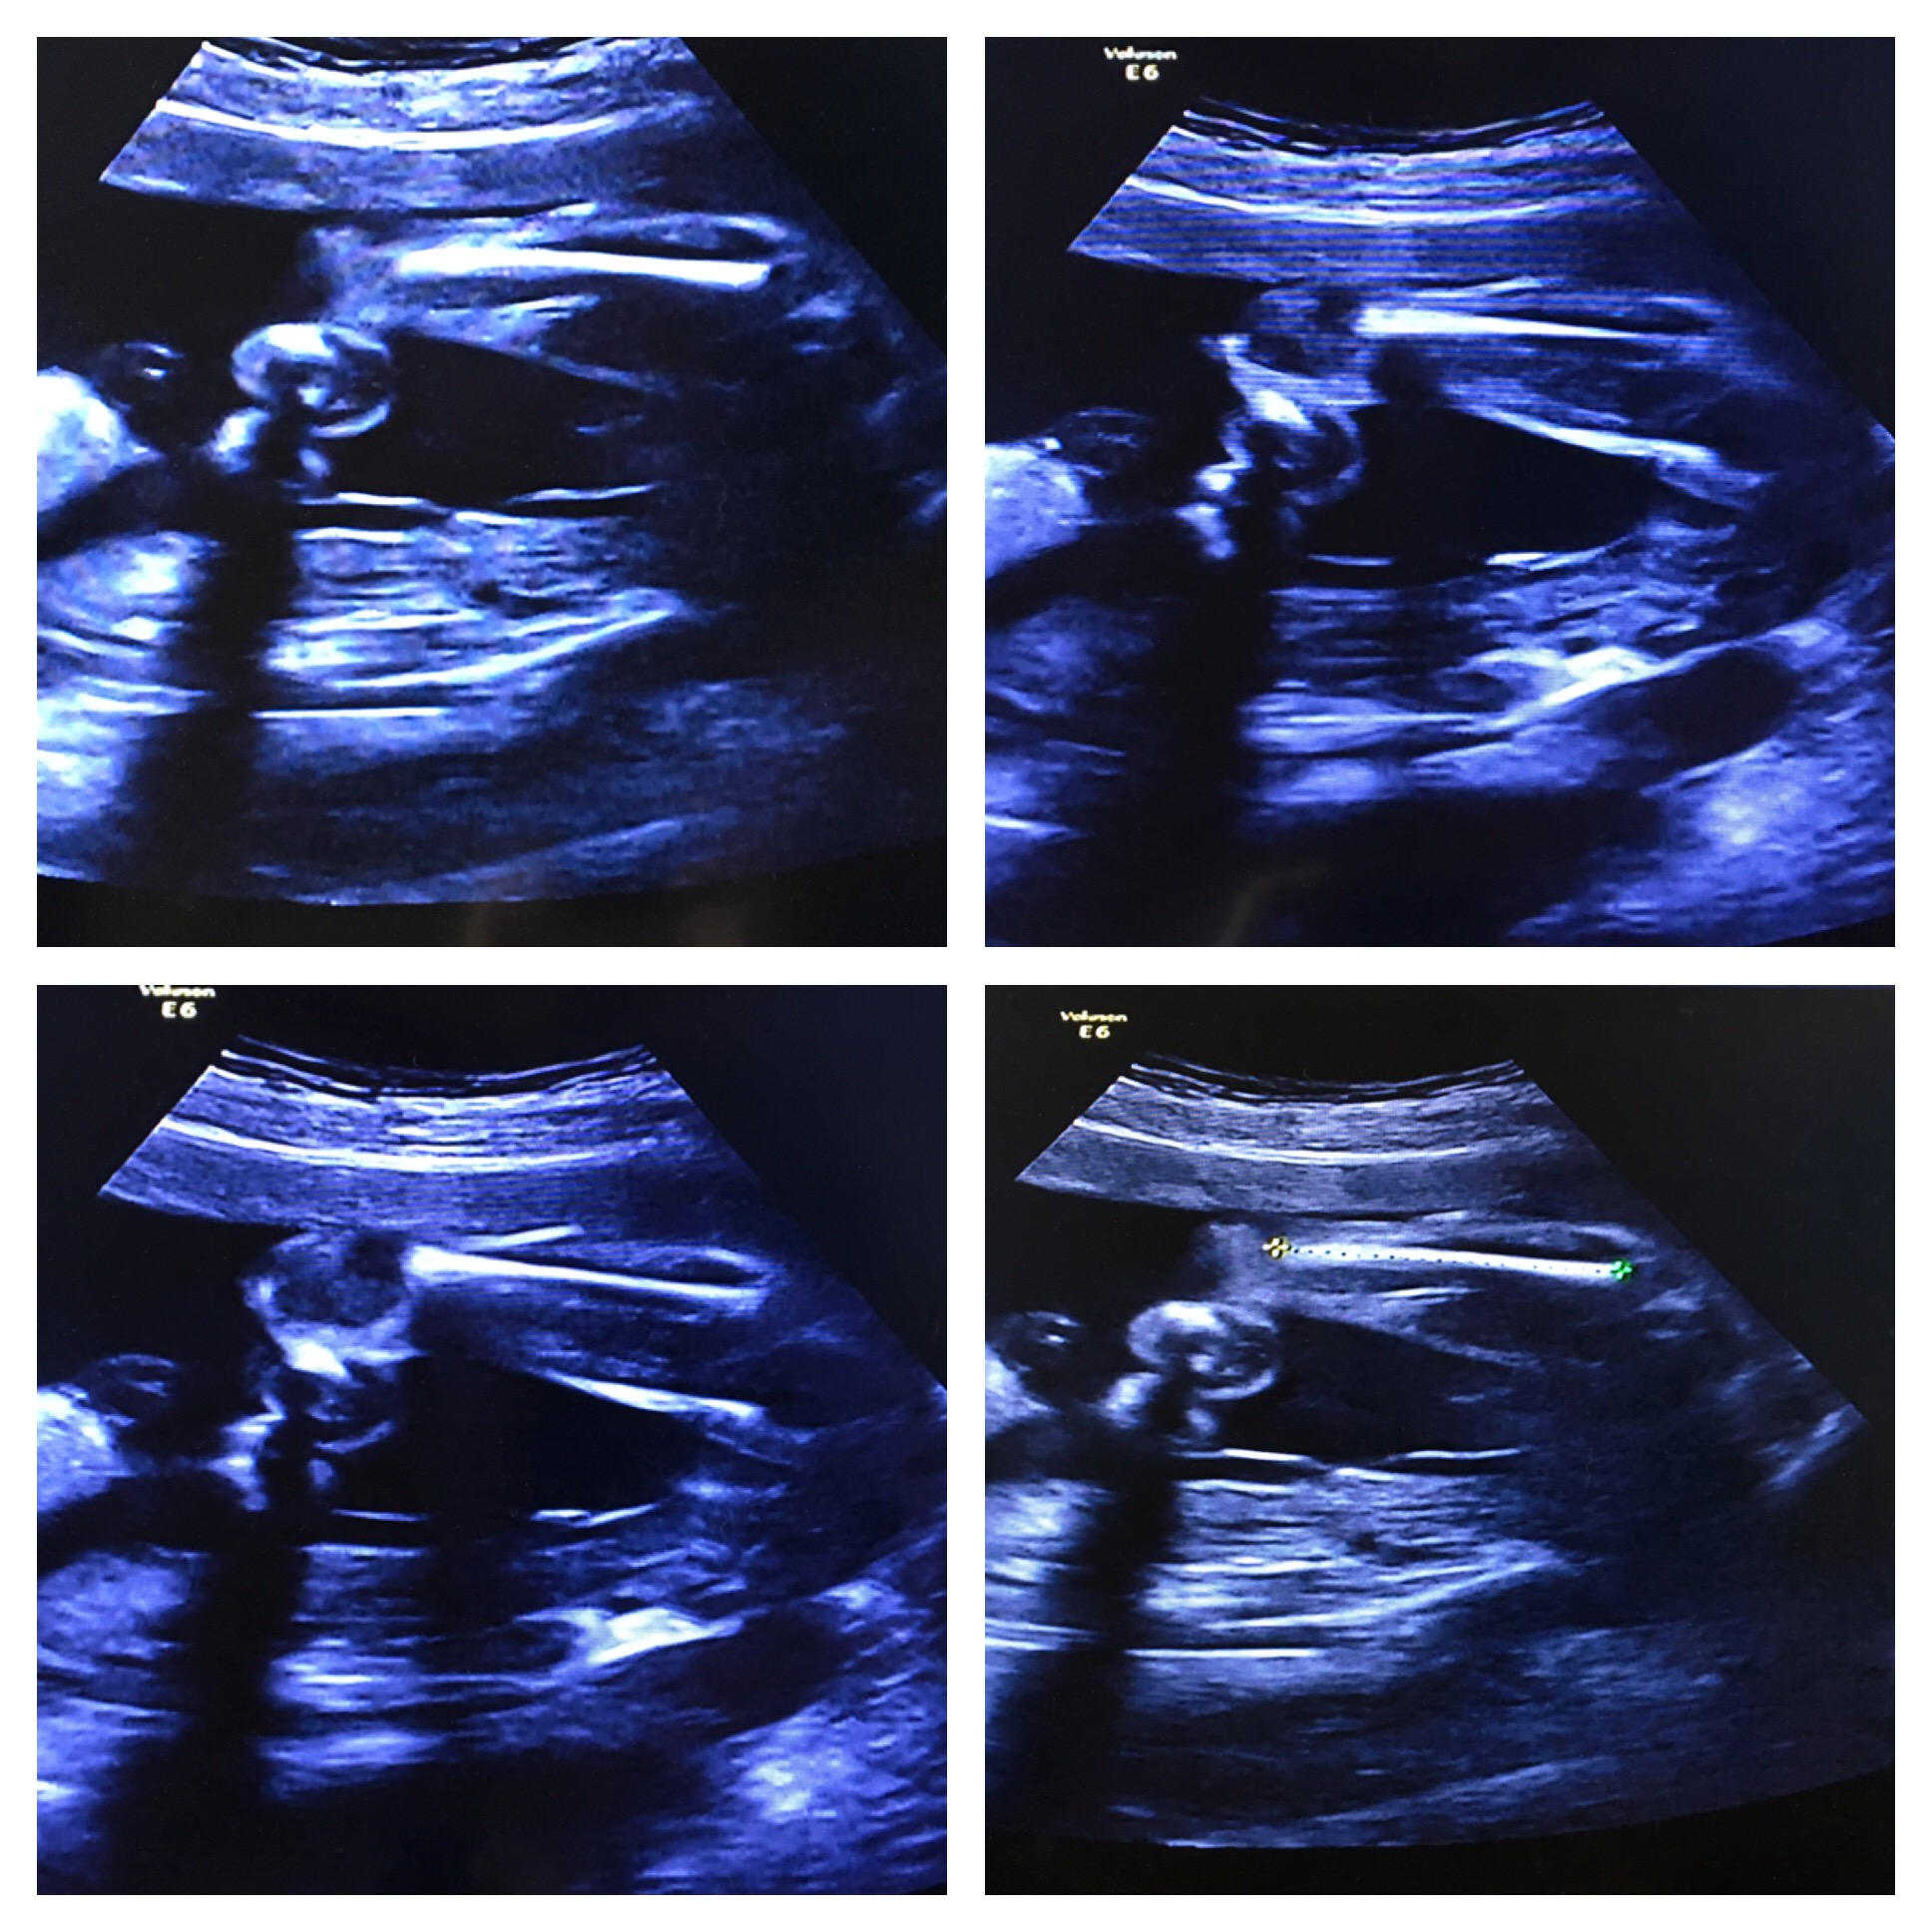

We are team green but I'm super curious! Photos are from the same ultrasound at 22 weeks. The potty shots are taken from my phone while the video was paused. Attachment 34349Attachment 34350

Did tech say if chord was between legs? if not im actually gonna guess boy :)

I would guess boy. I think I can see something in the 1st and 4th shots.

Between 1-2 seconds in you can see a nice little penis there :) Also at around 3 seconds it pops up.